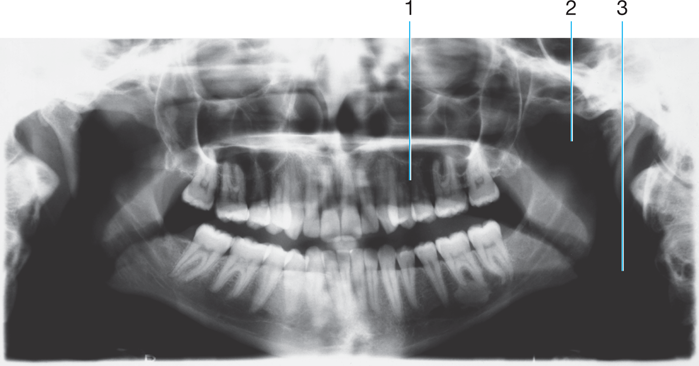

1.

Full metal crowns form bridge abutments

Identify the age of this patient

Age 12

Sharp projection of the maxilla located at the

anterior and inferior portion of the nasal cavity.

Radiolucent/Radiopaque?

Nasal Spine

Radiopaque

Age 8

Rounded prominence of bone that extends

posterior to the third molar region.

Maxillary Tuberosity #2

Identify the following:

(tube-like passageways through bone supplying blood vessels and nerves to maxillary teeth and bone, appear as narrow bands)

Nutrient Canals in Max Sinus